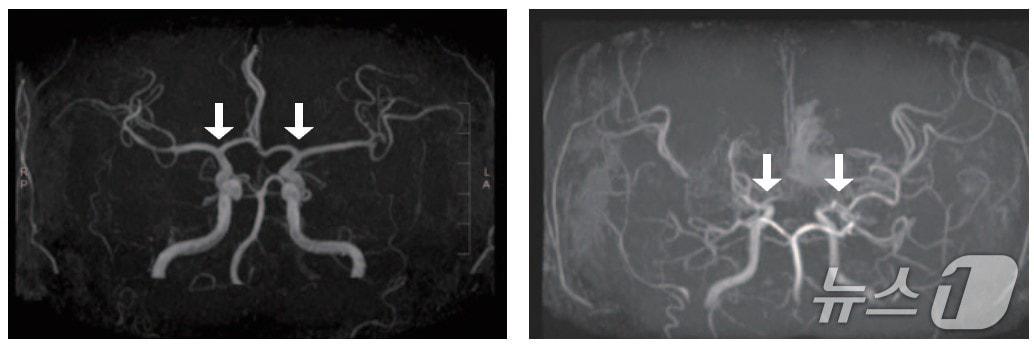

본문 이미지 - (왼쪽부터)정상 및 모야모야병 환자의 뇌혈관.(서울대병원 제공)

(왼쪽부터)정상 및 모야모야병 환자의 뇌혈관.(서울대병원 제공)